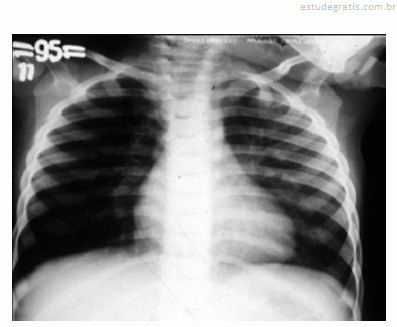

Um lactente de quatro meses de idade cronológica, nascido prematuro de vinte e nove semanas gestacionais, apresentou, durante o inverno, febre, tosse e dificuldade respiratória nos últimos três dias antes de ser levado por sua mãe à emergência pediátrica. A mãe relatou que a criança nunca havia apresentado um episódio semelhante a esse. O calendário vacinal mostrou que a criança recebeu duas doses da vacina antipneumocócica decavalente, porém não recebeu palivizumabe. O exame físico da criança mostrou desidratação, taquipnéia, retração intercostal e sibilos inspiratórios e expiratórios. O resultado do hemograma solicitado pelo médico revelou hematócrito de 40%, concentração de hemoglobina de 13 g/dL, 9.000 leucócitos/mm3, 55% de linfócitos, 34% de neutrófilos, 2% de eosinófilos, 1% de basófilos, 8% de monócitos, 340.000 plaquetas/mm3. O médico solicitou radiografia de tórax da criança, cuja imagem é apresentada na figura.

O diagnóstico dessa criança é de bronquiolite viral, sendo o principal agente etiológico o vírus sincicial respiratório.Comentários